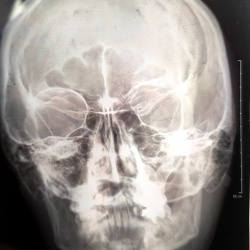

Множественная миелома? Гистиоцитоз? Гиперпаратериоидная остеодистрофия?